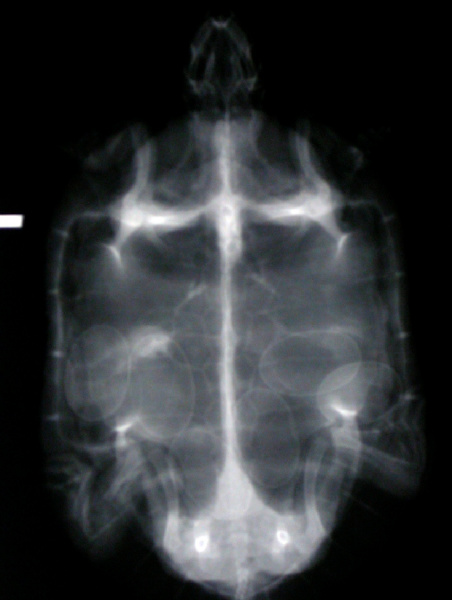

A veterinarian familiar with reptiles must examine these animals. They will conduct a physical examination and palpation, blood tests, and radiographs (X-rays) to facilitate a proper diagnosis.